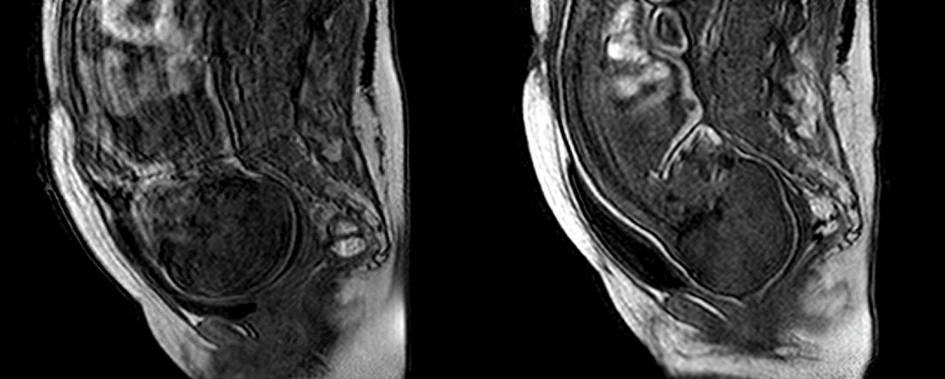

Des études sur le développement de l’anatomie cérébrale fœtale, réalisées à l’aide d’IRM au sein de l’Université Paris-Sud XI, ont permis d’explorer et de visualiser ce processus durant deux ans. Il a ainsi été possible de mesurer la densification des fibres cérébrales, de suivre la mise en place des voies d’information et de détecter l’apparition de connexions entre neurones au niveau du cortex.

Grâce à l’IRM, le processus de naissance a été étudié à l’Université Clermont Auvergne, non sans l’espoir de modéliser de manière plus fidèle la biomécanique obstétricale de l’accouchement normal. Les premières observations ont permis de découvrir les mécanismes présidant à la séquence de modelage du crâne et à la déformation cérébrale temporaire qui l’accompagne : le liquide céphalo-rachidien migrant vers la fosse postérieure, la faux du cerveau et la tente du cervelet qui procurent un système complexe de contraintes internes à l’architecture des os du crâne, qui ne sont pas soudés à cet âge et vont pouvoir se chevaucher, faisant de la « tectonique » du modelage du crâne une illustration de l’intelligence de la nature et des processus mis en place sur des millions d’années pour faciliter ce passage vers la vie ex utero.